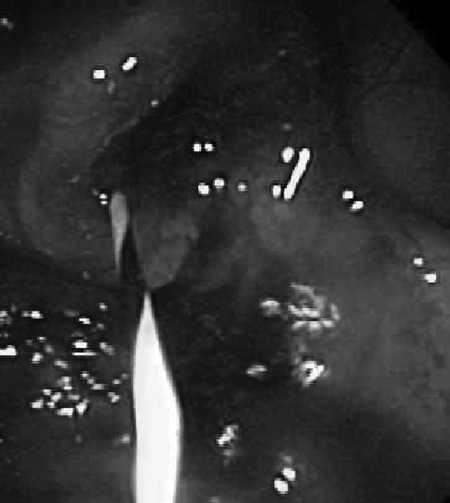

Figure 2.

Colonoscopic view of obstructing lesion.